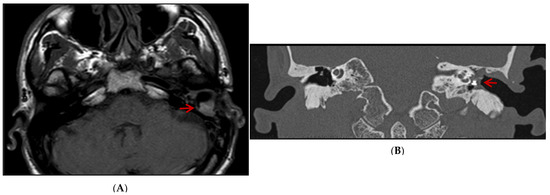

Based on clinical examination, an ear canal inflammation, along with myiases protruding from the external auditory canal, a non-marginal post-inferior perforation of the left eardrum, and a thick complete graft were observed. MRI demonstrated scarring lesions of the myiasis filling the middle of the ear space (Figure 1A). A CT scan showed the left middle ear filled with tissues enclosing the ossicular prosthesis (Figure 1B). He then underwent treatment, including fulfilling the ear cavity with topical ivermectin (5 crushed tablets of 3 mg) and Vaseline covered by an occlusive dressing for 48 h. An aspiration performed right after this intervention led to the isolation of several tens of maggots from the mastoid cavity. Patient care was continued on an outpatient basis with borated hydrogen peroxide ear baths twice a day for 7 days. Two weeks later, the patient felt an insect entering the left ear’s external auditory canal, crawling and making noise for 10 min without being able to pull it out. A bloody otorrhagia, otalgia, and scratching appeared 2 days after this event, leading to referring the patient again to the emergency department resulting in receiving the same treatment as two weeks ago. Following the observation of a teeming mass of maggots at the top of the external auditory canal close to the eardrum, they were aspirated the next day. No otorrhagia was observed after two days. The outcome was favorable within 3 months, and no relapse was reported by the patient. It is worth mentioning that the patient consulted for a dengue infection diagnosed by NS1 antigen detection a few days after the appearance of myiasis, without an obvious correlation between both medical events.

Figure 1.

MRI axial (A) and CT scan coronal (B) images: scar lesion filling the left middle ear of the patient (highlighted by red arrow) compared to the right ear.